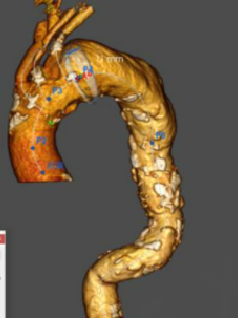

★ 病例5:解剖变异

(右位弓,迷走右锁骨下动脉)

释放方法和正常手术相同,但方向相反,需要调整。特别是分支的走向测试了该装置适应不同解剖结构的能力和便利性。

术后血管造影显示,所有分支方向与患者血管解剖结构匹配,尤其是无名动脉,外侧成近90°角,无内漏发生。随访显示所有分支通畅,无扭曲或迂曲,无卒中及内漏。